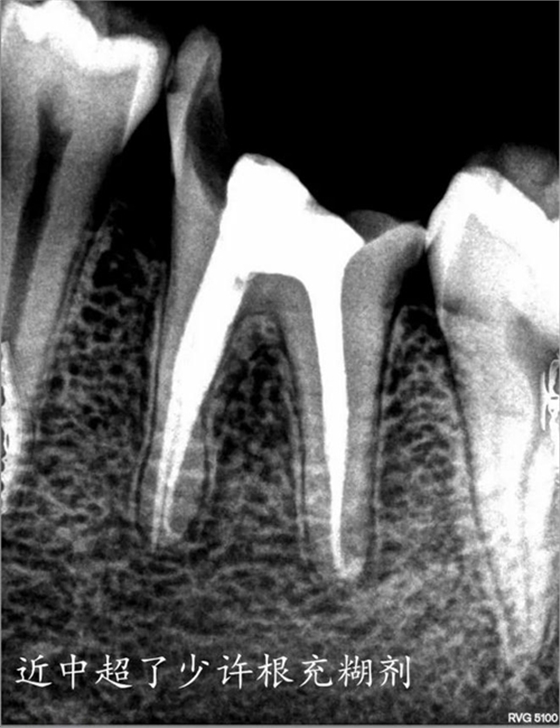

部分病例: